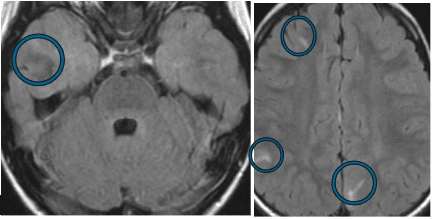

Some diseases that vaccines prevent can cause epilepsy. For example, whooping cough and measles can hurt the brain and cause serious illness or death. The MRI images below are from a previously healthy, fully vaccinated child, with whooping cough. The whooping cough caused bleeding and injury throughout the brain, causing medication-resistant epilepsy (the areas of injury are circled and are only an example of the many areas that were injured).